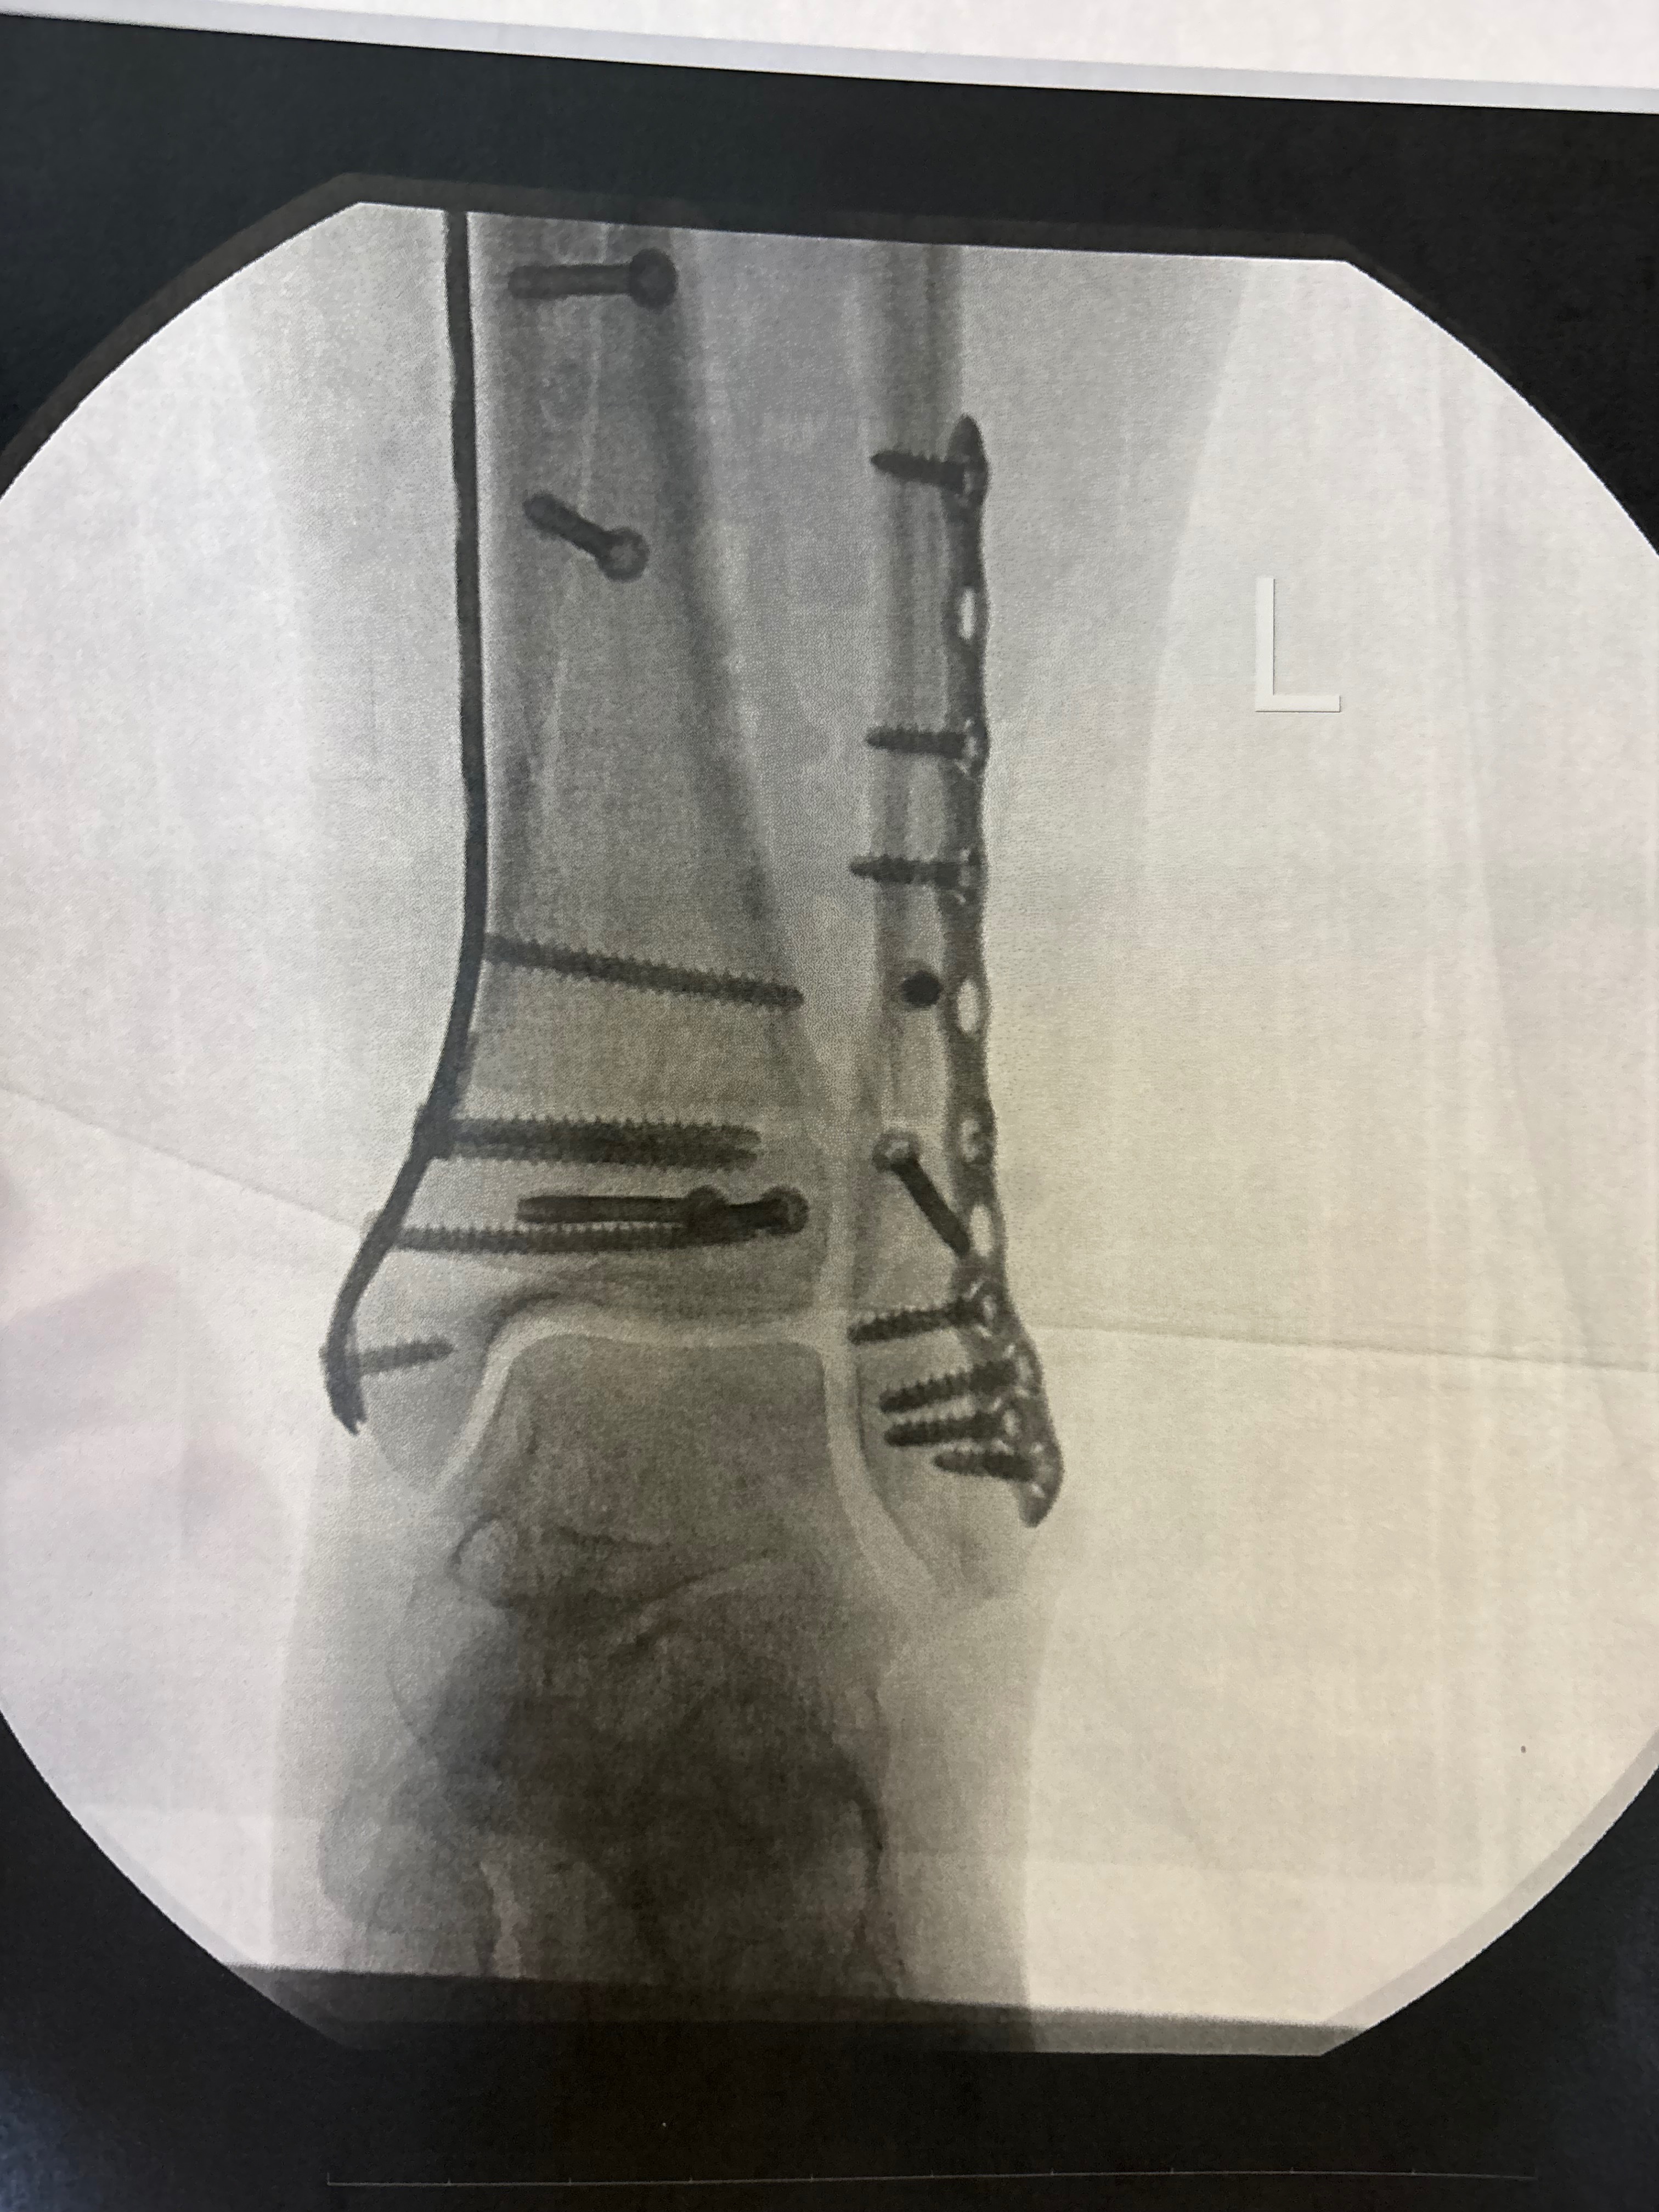

I was rushed to the ER. My partner en route, surrounded by strangers and in pain, I was out of my depth. After an X-ray and some morphine, I was told three things: that both bones in my left leg were broken, that my pain made sense, and that I would need to have surgery.

They sedated me, repositioned my floating bones, and put them in a temporary cast till my surgery. It hurt to move.